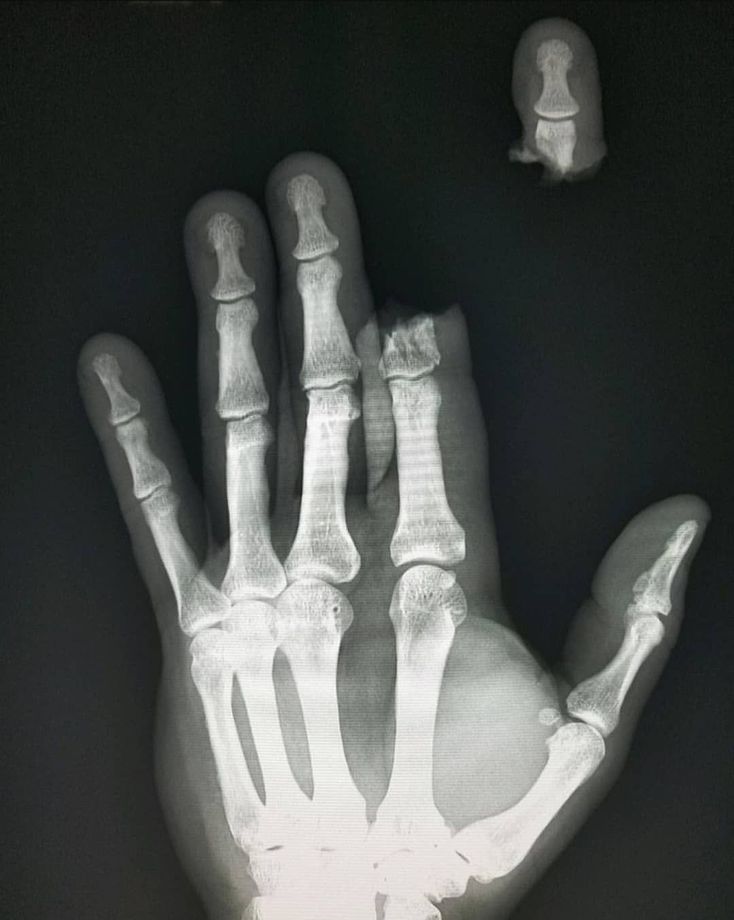

. Management of finger amputations varies in relation to the number of fingers amputated, the phalangeal level at which the amputation has occurred and the integrity of the soft tissue remaining. . After obtaining the X-rays the surgeon determines the degree of damage to the fingers and hands. The surgical approach takes into consideration the balance between finger amputation and replantation, relative to the functional outcome and cosmetics. In case of fingertip amputation, the surgeon removes the dead tissue, shortens the bone if necessary, and closes the extremity with a tissue flap. If the amputation is extensive (involving the phalanges and soft tissue), the detached extremity is preserved under sterile and moist condition for a possible replantation. A soft tissue graft taken from other body parts may be required in case of abundant tissue loss. The goal of surgery is to create a suitable anatomy to eventually fit a finger prosthesis if replantation is not possible. . . Tag a friend and follow us @medicalpedia for more extreme cases!